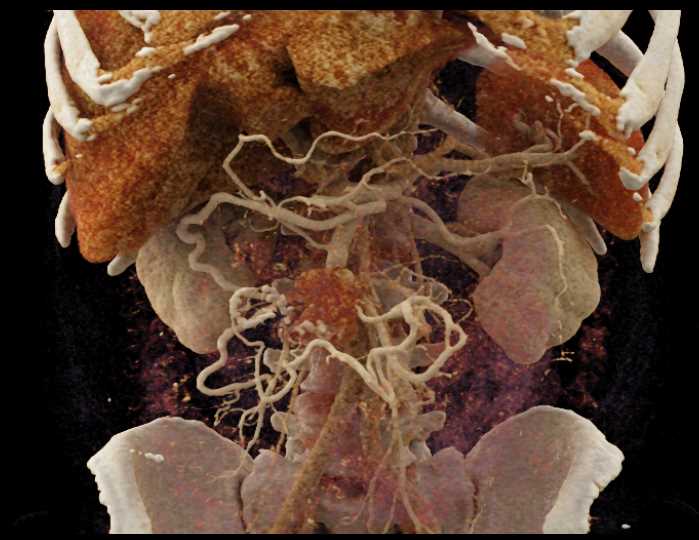

Carcinoid Tumor with Desmoplastic Reaction